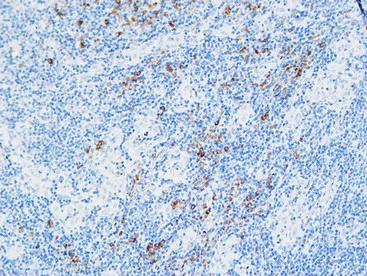

MPO Rabbit Polyclonal Antibody

Cat: APRab14056

Size1:50μl Price1:$118

Size2:100μl Price2:$220

Size3:500μl Price3:$980

Size2:100μl Price2:$220

Size3:500μl Price3:$980